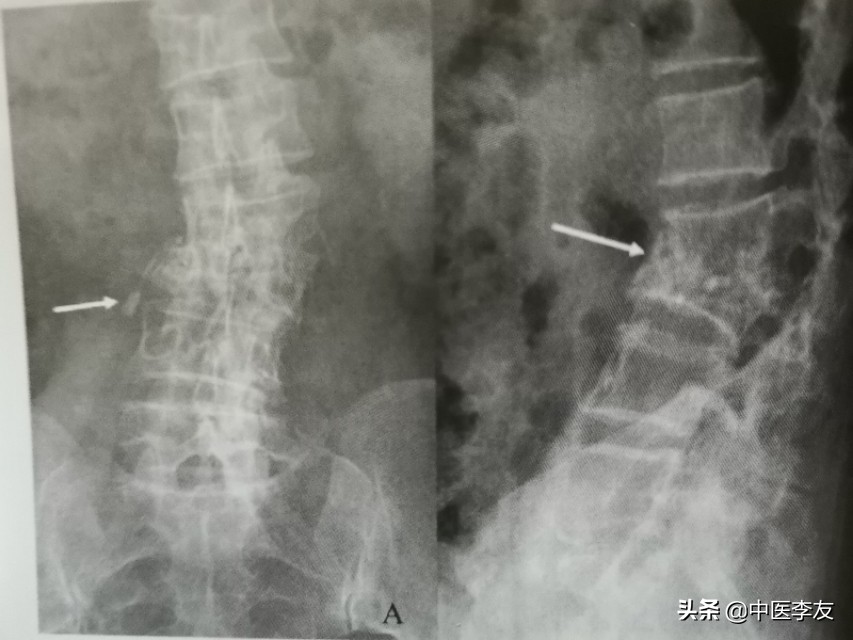

1.X线:①骨质破坏:表现为低密度骨质缺损区,边缘无硬化。

②椎间隙变窄或消失,因椎间盘及软骨终板被破坏,椎间盘破坏严重者可导致相邻的椎体融合在一起,为诊断脊椎结核的重要依据。

④冷性脓肿:腰椎结核可形成腰大肌脓肿,表现为腰大肌呈弧形向外突出高密度影,胸椎结核形成椎旁脓肿,表现为胸椎两旁梭形软组织肿胀高密度影,颈椎结核形成咽后壁脓肿,表现为咽后壁软组织影增宽,并呈弧形前突,较长时间的冷性脓肿可有不规则钙化。

依据骨质最先破坏的部位可分为:①中心型,又叫椎体型,表现为椎体内圆形或不规则形的骨缺损区,边缘不清,内可有小泥砂状死骨,后期椎体常塌陷变扁或呈楔形,甚至整个椎体消失,此时骨质破坏和死骨不好观察。

③韧带下型(椎旁型),病变在前纵韧带下扩展,常累及数个椎体,表现为椎体前缘糜烂性或凹陷性破坏,早期椎间盘保持完整,后期可同时累及多个椎体及椎间盘。

④附件型,较少见,可累及棘突、横突、椎板、小关节突,表现为骨小梁模糊,骨皮质中断,密度减低,累及关节突时常跨越关节。